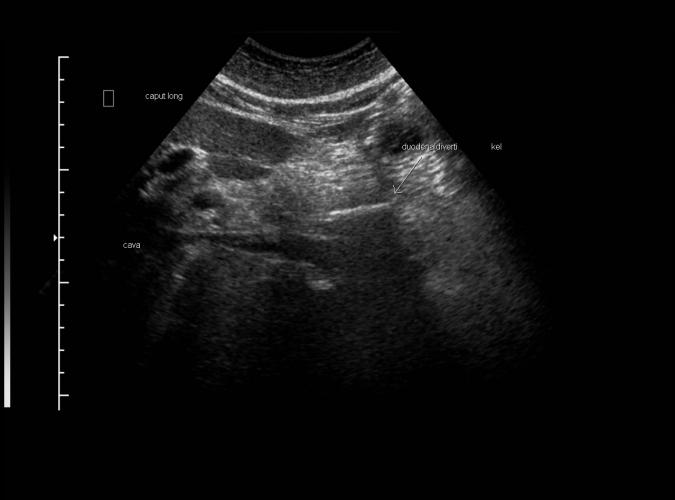

Long. Caput pancreas med duodenaldivertikel (linjärt eko markerat med pil) Trans bild 4a, 4c